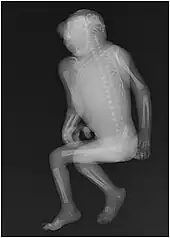

| Illustration of an anencephalic fetus | |